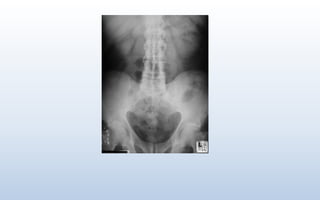

Irregular Fuzzy Outline of Sacroiliac Joints

Irregular Fuzzy Outlineof Sacroiliac Joints